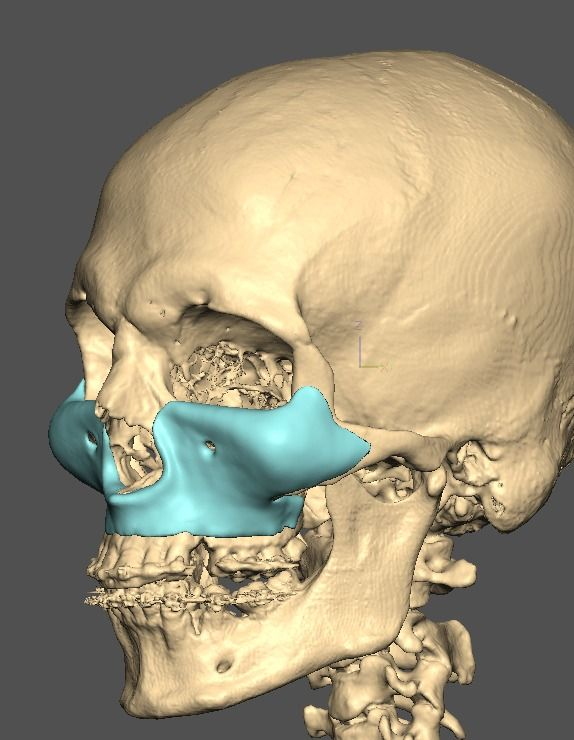

I know a guy who designed this for himself in collaboration with an asian implant company.

Not the final product yet, he is making adjustments as we speak.

Found a surgeon willing to insert it.

Giant and Eppley were the inspiration